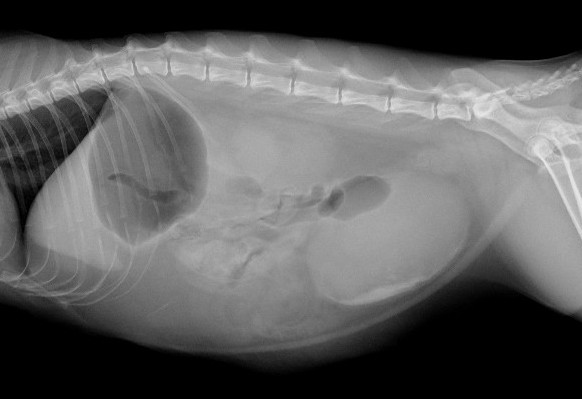

レントゲンとエコー検査にて膀胱内に砂粒の存在と尿道の閉塞を確認

before